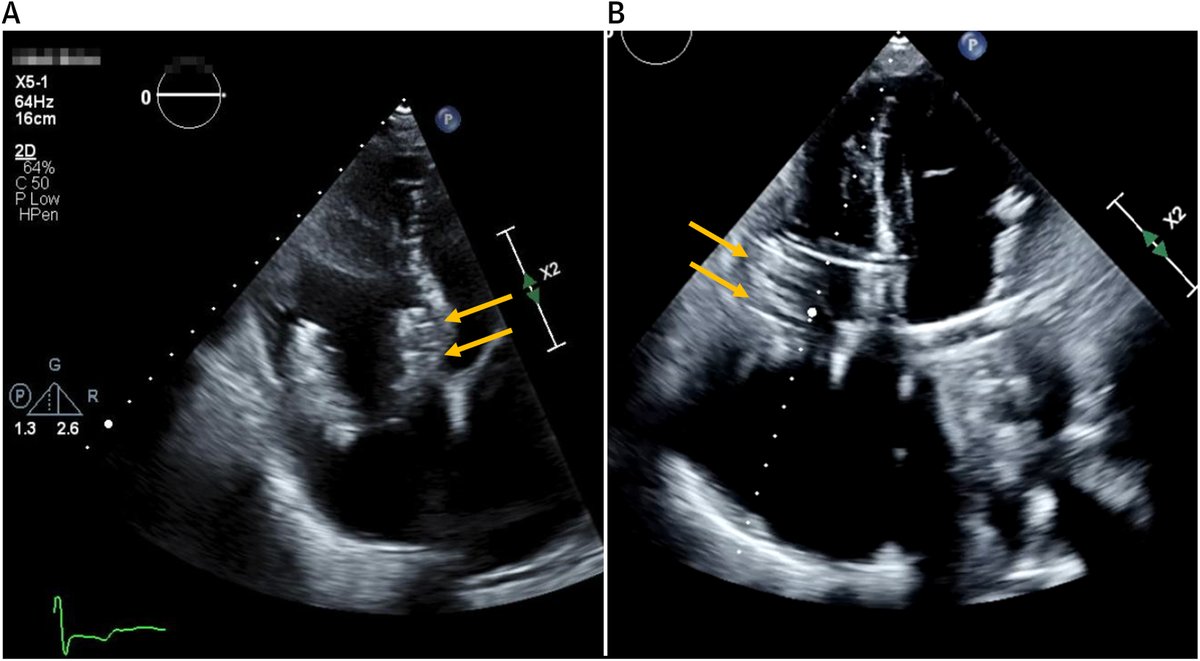

FANTASTIC MUST-READ #JACCIMG @JACCJournals SOTA review on Post #Evoque #TTVR Echo #TTE imaging. Comprehensive, practical! Download full paper here FREE for a LIMITED TIME! https://t.co/lfhJ0khJAw https://t.co/DgyCXnMOOF